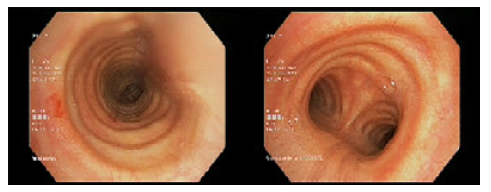

<p>During her stay in the PACU, approximately 20 minutes after the end of surgery, the patient presented several episodes of hemoptysis accompanied by dyspnea and oxygen saturation of 95% which improved with supplemental oxygen at 2L through a nasal cannula. Pulmonary auscultation at that time was unremarkable and no subcutaneous emphysema was found in any location. The case was immediately discussed with the Pulmonology Department, which proceeded to perform a fibrobronchoscopy that showed an erosive, lacerated and bleeding injury of 1.5cm in length on the posterior wall of the trachea and 5cm from the vocal cords (<xref ref-type="fig" rid="f1">Figure 1</xref>). However, due to the active bleeding, it was not possible to establish the depth of the lesion in the thickness of the tracheal wall.</p>

<title>Initial fibrobronchoscopy.</title>

<p>After discharge, the patient was referred to the Thoracic Surgery Department and at her first follow-up, 10 days after the incident, it was found that she was asymptomatic and continued antibiotic treatment until 10 days had elapsed. During the second follow-up, 20 days after the tracheal laceration, a new fibrobronchoscopy was performed, which showed the tracheal mucosa had healed (<xref ref-type="fig" rid="f2">Figure 2</xref>), so the Thoracic Surgery Department discharged her and indicated that she should be followed up by her primary care physician.</p>

<title>Fibrobronchoscopy after hospital discharge.</title>